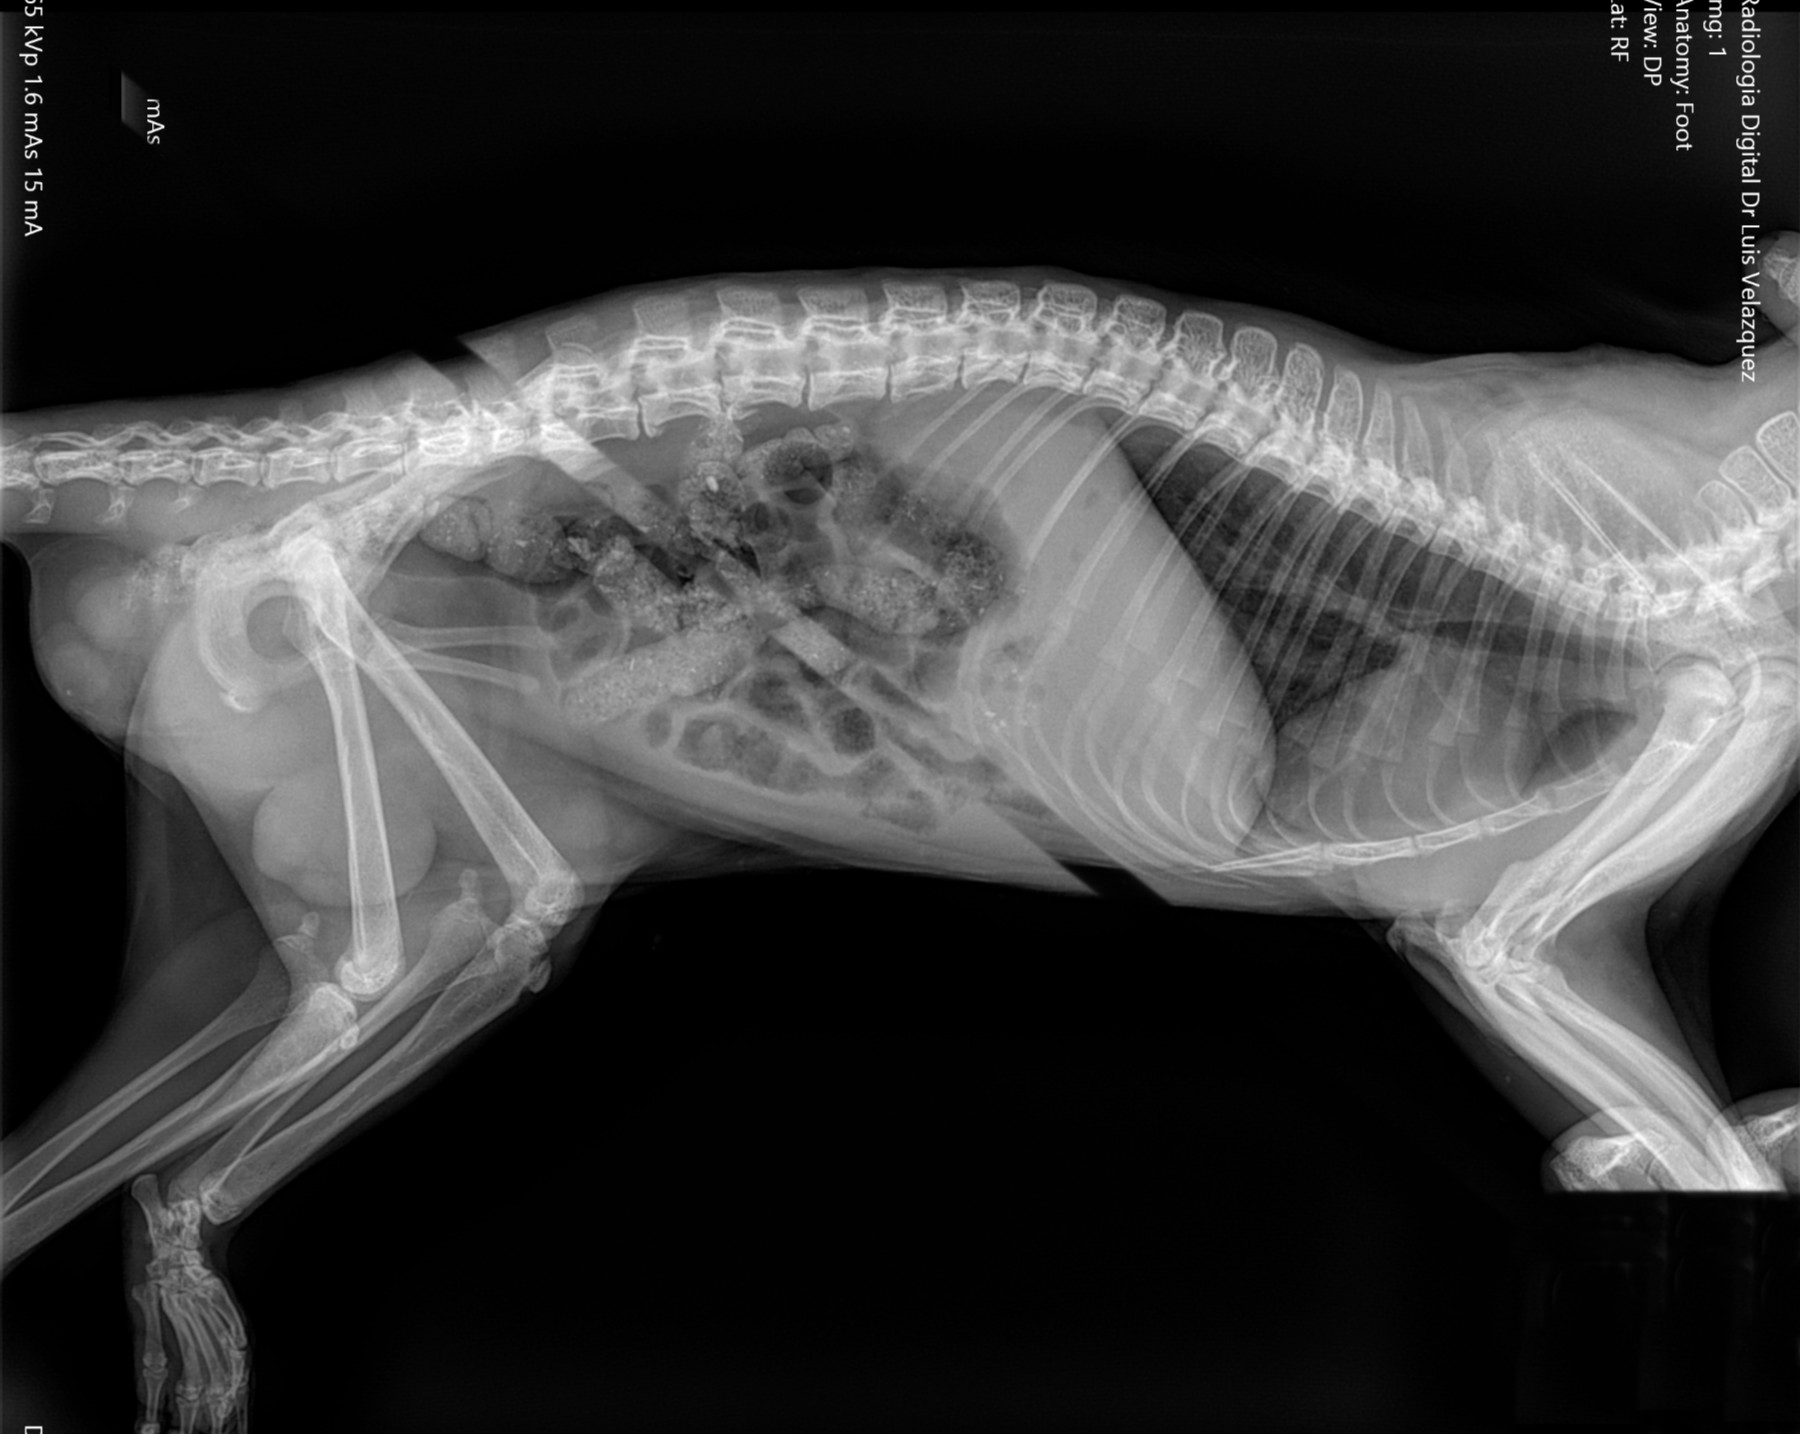

Cambios Térmicos en las Extremidades de Caballos,

Asociados a Golpes y su Evaluación por Termografía.

Los caballos de salto, en competencia, pueden derribar obstáculos y lastimarse. Si se golpean, no siempre claudican. Considerando al calor como un signo de inflamación, se evaluaron los cambios térmicos de 6 áreas de las extremidades torácicas y pelvianas de 23 caballos de salto en nivel de competencia de 1.05 a 1.60 m de altura, por medio de termografía durante 4 días de competencia (N=2208 áreas).